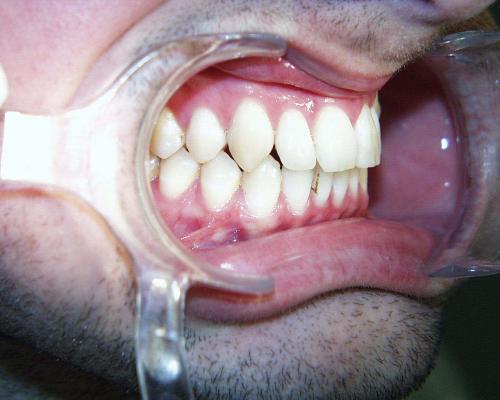

Nach der Behandlung

(Dauer der aktiven Behandlung: 1 Jahr, 11 Monate)

Eine langjährige Stabilisierung der Frontzähne mittels eines Kleberetainers ist unverzichtbar. Die Miniimplantate sind auf dem Foto unten links noch sichtbar; sie können bald nach dem Abnehmen der festen Zahnspange in einem kleinen chirurgischen Eingriff ebenfalls entfernt werden.